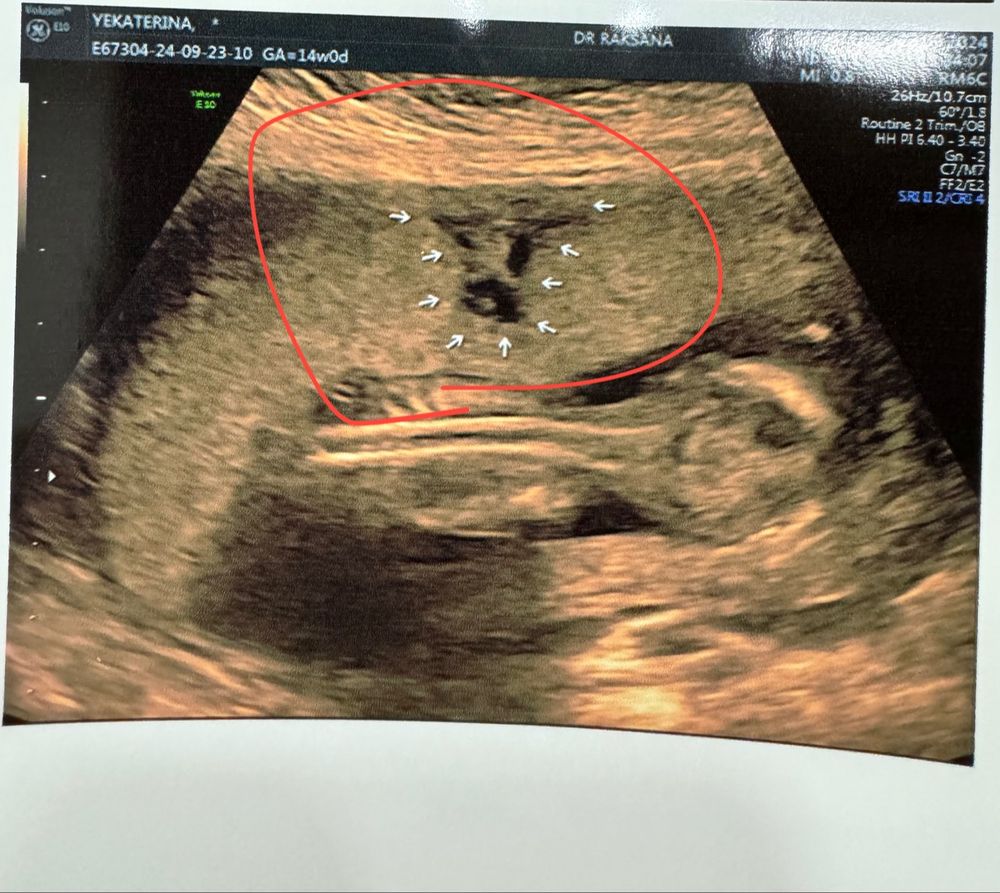

Гематома 2 триместр

Гематома 2 триместр 114 фото